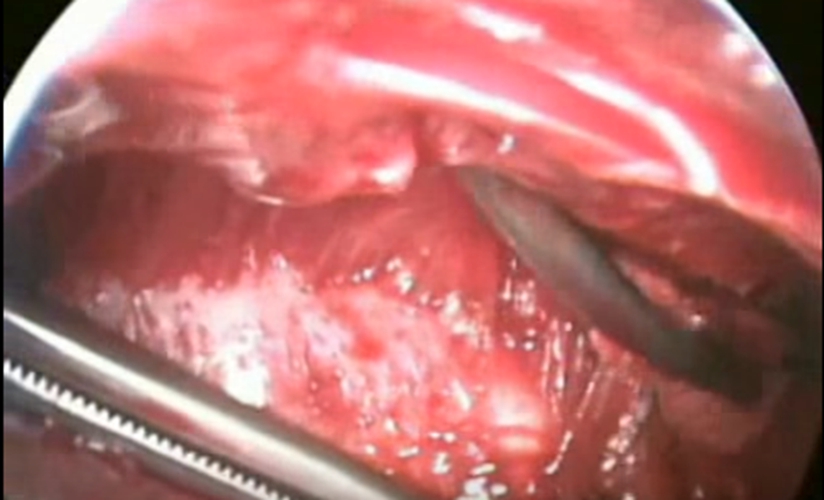

結核性胸膜炎胸腔鏡

結核性胸膜炎胸腔鏡的